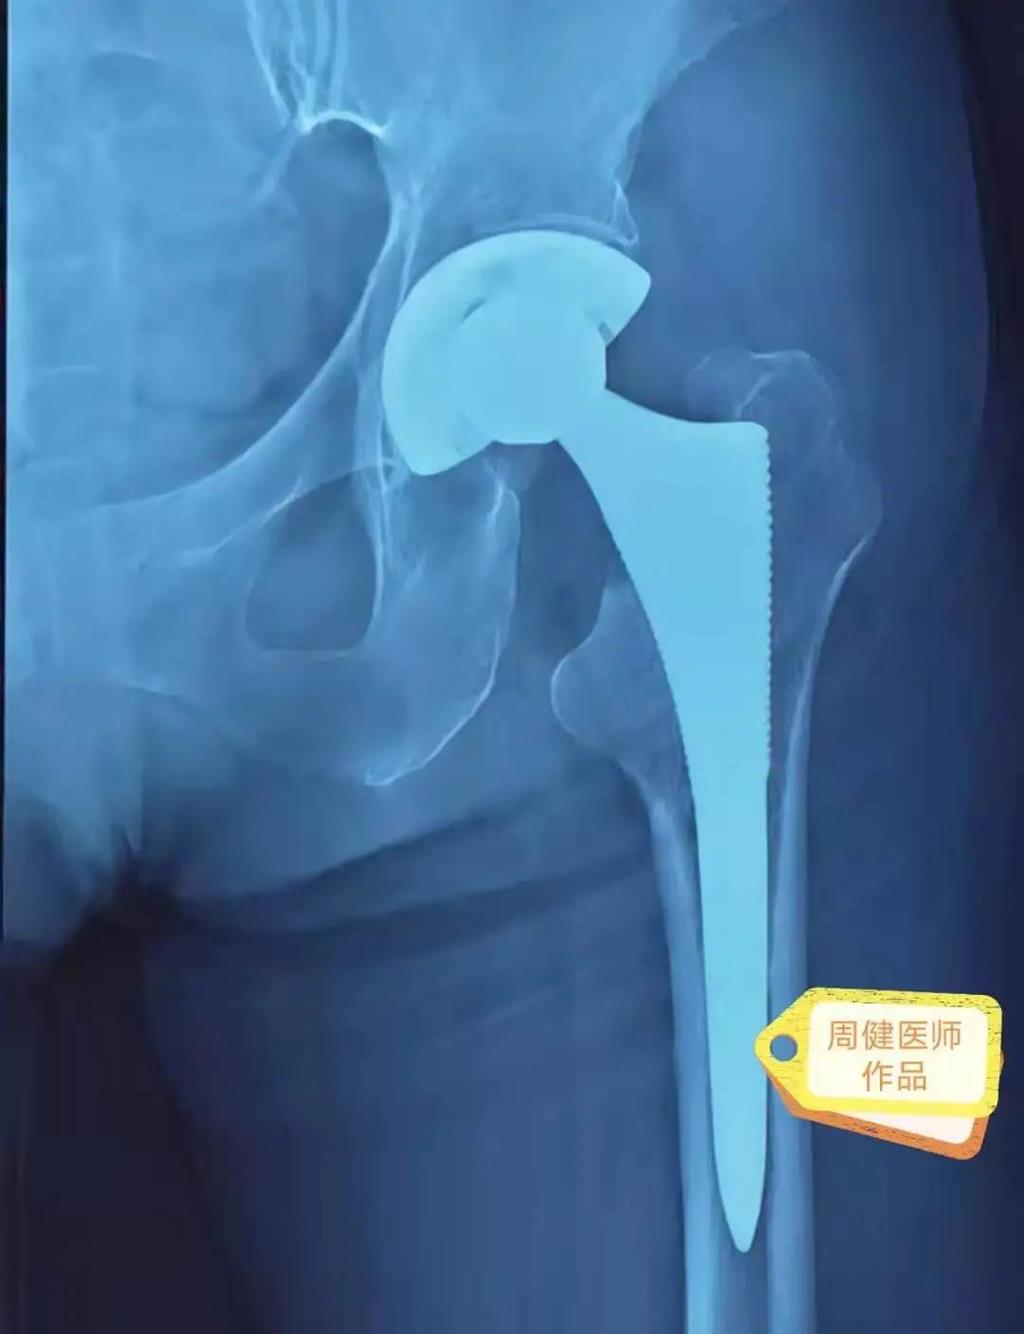

6月30日的“關(guān)節(jié)置換術(shù)”,患者是一位上了年紀(jì)的老人,苦于病痛折磨多年的他四處“求醫(yī)問(wèn)藥”,最后在多位專(zhuān)家醫(yī)師及病友地力薦下選擇了和平國(guó)際醫(yī)院,在醫(yī)師團(tuán)隊(duì)“偷天換日”般的手術(shù)后,老人成功告別了苦纏多年的病痛。

周健說(shuō),這場(chǎng)“關(guān)節(jié)置換術(shù)”對(duì)于他們團(tuán)隊(duì)而言其實(shí)算是比較普通的手術(shù),因?yàn)樽鲞^(guò)很多同類(lèi)的手術(shù),成功案例繁多,因此在手術(shù)操作上有較多地實(shí)操經(jīng)驗(yàn)。“不過(guò)話(huà)雖如此,作為醫(yī)生我們對(duì)于每一場(chǎng)手術(shù)都會(huì)全力以赴,這是為醫(yī)者的職責(zé)也是義務(wù)。”